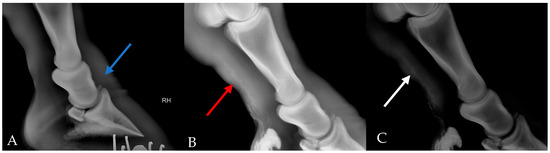

2.6. Survey Radiograph, Lymphangiogram and Ultrasonography

3.2. Diagnostic Imaging Results